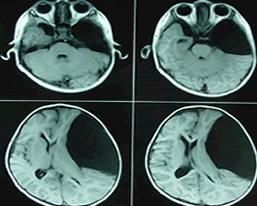

1.頭顱CT檢查

相對於腦脊液呈等密度(相對於腦實質呈低密度)占位病變,囊壁無強化,周圍無水腫帶,局部腦組織受壓變形或移位,位於中線者可有梗阻性腦積水。

2.頭顱MRI(磁共振成像)檢查

低T、高T信號、與CSF信號相同的病變,區別於顱內繼發感染後的囊腫和炎性肉芽腫。